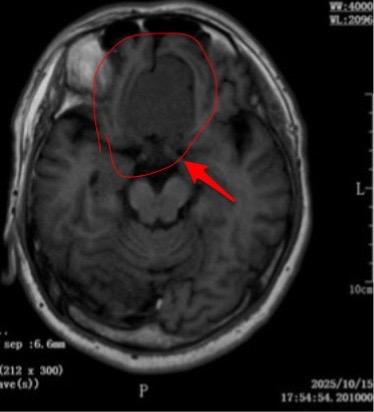

这个是脑膜瘤吗?58岁男性,洛阳市人。今年10月份单位作体检,发现这个瘤。病人无明显症状,无头痛,无视力下降。 是脑膜瘤吗? 脑膜瘤是脑部发病率最高的原发肿瘤,绝大多数脑膜瘤是良性肿瘤,不是所有的脑膜瘤都需要作手术。